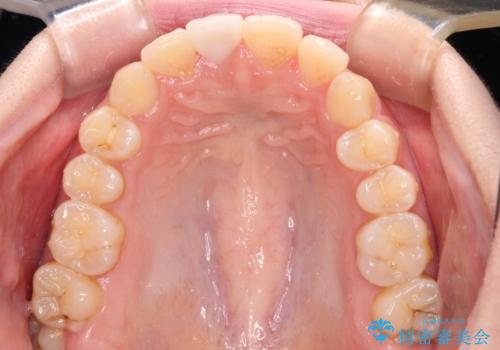

- 転んで前歯が欠けてしまったとのことで来院された患者様です。

転んで前歯の先端1/3ほどが欠けており、近医にて応急処置としてコンポジットレジン修復がされていました。

審美性や舌触り、今後の歯への負担などを考え、オールセラミッククラウンにて補綴治療を行うこととしました。